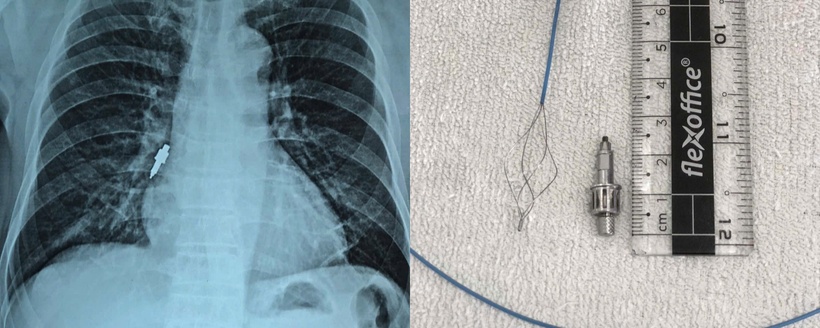

Sau đó bệnh nhân xuất hiện ho nhẹ kéo dài. Đến ngày hôm sau, ho tăng nhiều khiến gia đình đưa đi khám và chụp X-quang, phát hiện dị vật nằm trong phế quản phải dài 2,5cm nên đã chuyển cụ ông vào bệnh viện.

Bệnh nhân được chỉ định nội soi phế quản cấp cứu để gắp dị vật. Tuy nhiên, quá trình lấy dị vật gặp rất nhiều thách thức do dị vật trơn, bằng inox, kích thước lớn, đường kính chỗ to nhất lên đến 1 cm, dài 2,5 cm, mắc sâu và chặt vào phế quản phải. Không thể gắp được bằng kìm sinh thiết – loại thường dùng với các dị vật thông dụng như hạt lạc, xương cá…

Sau nhiều nỗ lực, ê-kíp đã gắp thành công dị vật, rút ra ngoài nguyên vẹn. Sau đó, phế quản được bơm rửa sạch mủ và cặn máu trong lòng đường thở.

Hình ảnh X quang phát hiện dị vật (trái) trong phế quản bệnh nhân và sau khi đã gắp được dị vật (phải)